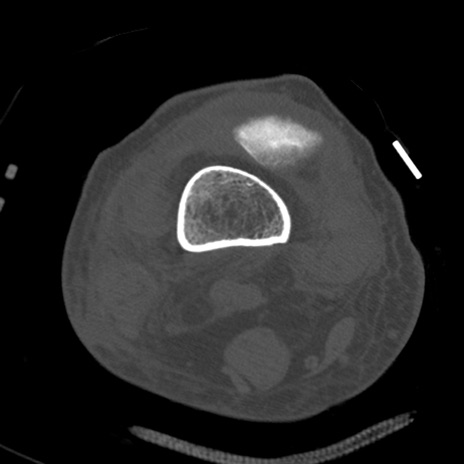

症例28 右膝関節CT(横断像)

右膝関節CT